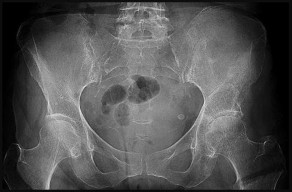

This patient has a dedifferentiated liposarcoma within a preexisting atypical lipomatous tumor. The imaging demonstrates a large fatty mass with increased internal septations proximally (the atypical lipomatous tumor) and a solid enhancing mass distally (the dedifferentiated portion). A biopsy reveals a high-grade liposarcoma. The other diagnostic responses do not reflect sarcomatous transformation of the lesion.

Surgical treatment of a high-grade sarcoma involves wide surgical resection. Radiation decreases local recurrence but does not clearly influence overall survival. The role of chemotherapy in high-grade soft-tissue sarcomas remains investigational; there is a modest (8%-15%) associated improvement in overall survival.

Intramuscular lipomas and atypical lipomatous tumors are treated with marginal resection alone. Radiation therapy for soft-tissue sarcomas may be given before or after surgery. When administered before surgery, patients have a higher wound complication rate but better long-term function attributable to lower rates of lymphedema, fibrosis, and contractures.